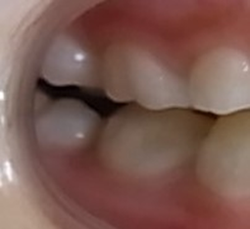

今回の場合、歯並びが悪い原因は 上顎が小さい事 でした。

拡大 矯正前 矯正後

診査・診断の結果、

上顎の大きさを約10ミリ大きくしなくてはならないことがわかりました。

今回の症例は、約6カ月ほどで改善しています。

しかし、拡大だけで将来の歯並びが良くなる訳ではありません。